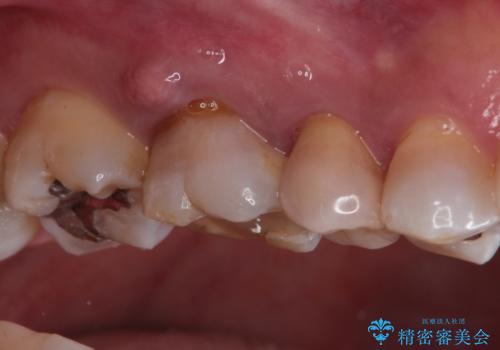

- 定期検診にて、奥歯の頬側歯肉にサイナストラクトが発見された患者様です。

根管治療から歯冠修復まで行っております。

サイナストラクト(瘻孔)から原因歯を特定し治療を行っております。根管治療を行った歯牙は破折リスクが高くなるため被せものによる治療を提案しております。